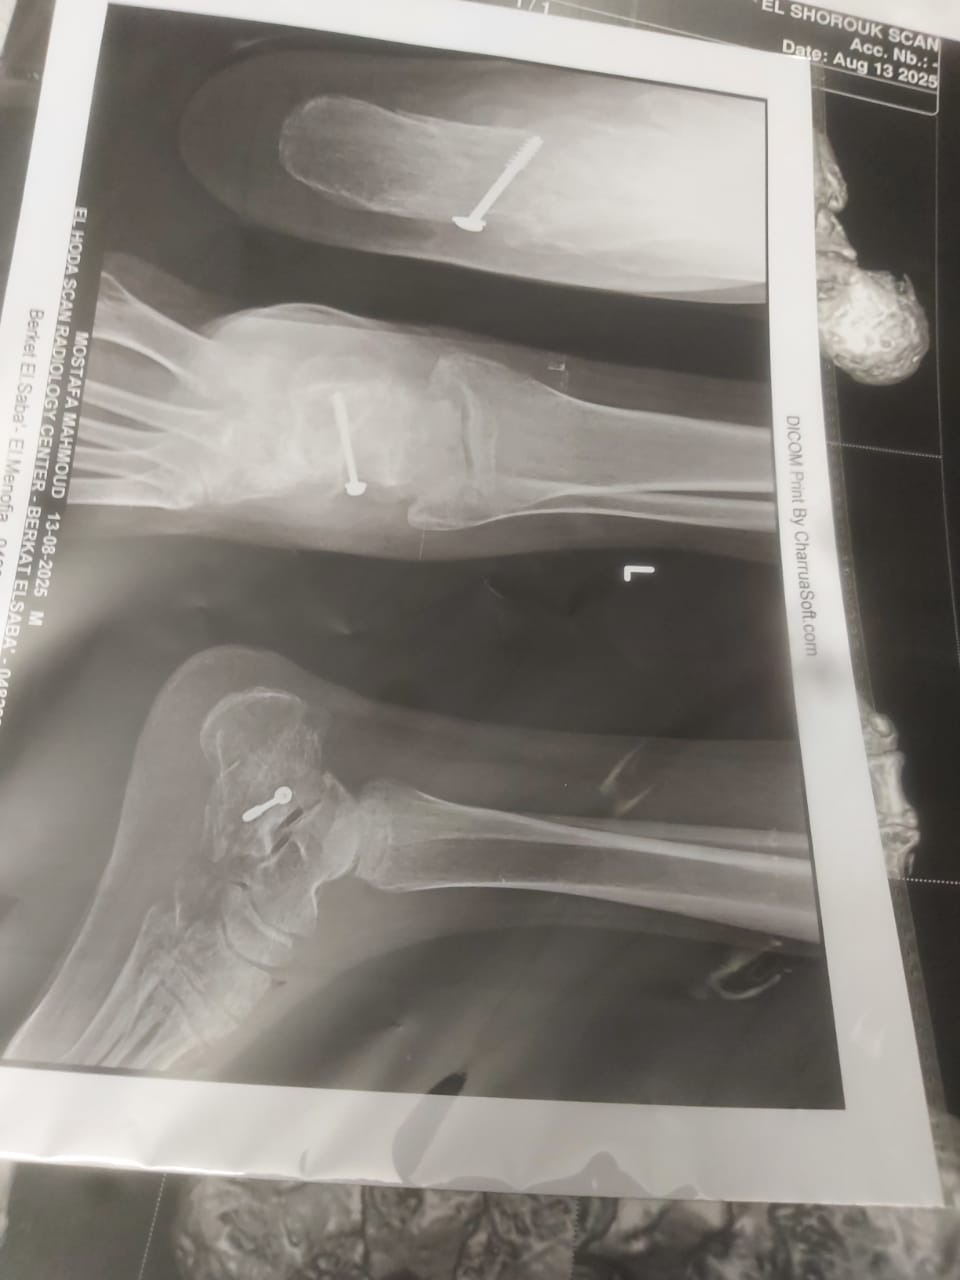

Mustafa’s survival came with a terrible cost. His leg was crushed, and after an emergency surgery, doctors placed a metal screw to hold it together. But now, that screw is causing severe infections and unbearable pain. He urgently needs another surgery to remove it, or the infection could spread and lead to permanent disability.